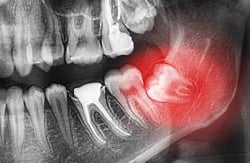

Extracción de muelas del juicio (terceros molares).

Extracción de dientes retenidos o supernumerarios.

Previene complicaciones mayores en hueso, encías o dientes vecinos